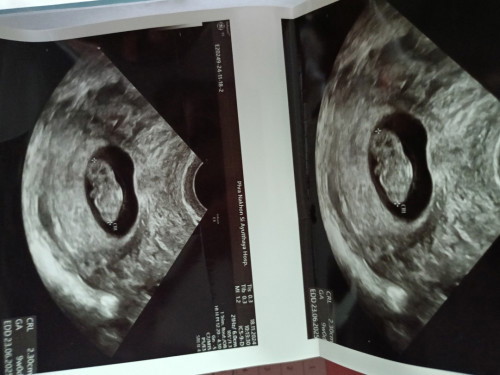

เพิ่งไปหาหมอมาเมื่อวานค่ะครรภ์ได้ 11 สัปดาห์คุณหมอคลินิกแรกแจ้งว่าเป็นครรภ์ไข่ปลาอุก ไม่มีตัวอ่อนอยู่ในท้อง ซาวด์ผ่านหน้าท้อง คุณหมอแจ้งให้ไปขูดมดลูก คุณแม่เลยไม่สบายใจไปอีกคลินิกใหม่ซาวผ่านช่องคลอด เห็นก้อนกลมเหมือนในรูป คุณหมอแจ้งว่าอีกอาทิตย์นึงมาตรวจใหม่ว่าใช่ตัวเด็กไหม คุณแม่คนไหนเคยเจอเหตุการณ์แบบนี้บ้างคะตอนนี้คุณแม่ไม่สบายใจมาก ไม่รู้เลยว่าตัวเองท้องหรือไม่ท้อง

รอนัดหน้าอีก1นัดก็ได้ค่ะ เเต่บ้านนี้ 9w เห็นเป็นตัวน้องเเล้วค่ะ